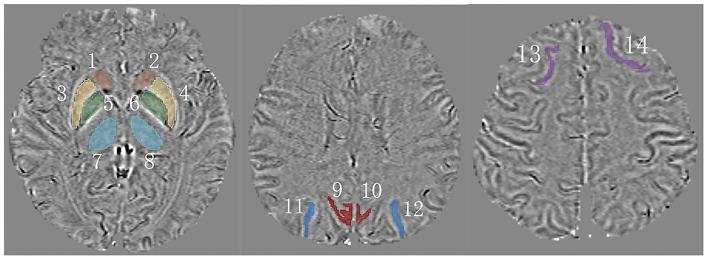

A total of 64 participants underwent magnetic resonance imaging (MRI) scanning and were separated into three groups, namely, CMB(+), CMB(-), and healthy controls (HCs). We compared their characteristics and susceptibility values of rich-club nodes [e.g., superior frontal gyrus (SFG), precuneus, superior occipital gyrus (SOG), thalamus, and putamen]. We then divided the CMB(+) and CMB(-) groups into subgroups of patients with or without MCI. Then, we analyzed the relationship between iron deposition and MCI by comparing the susceptibility values of rich-club nodes. We assessed cognitive functions using the Montreal Cognitive Assessment (MoCA) and quantified iron content using quantitative susceptibility mapping (QSM).

方法